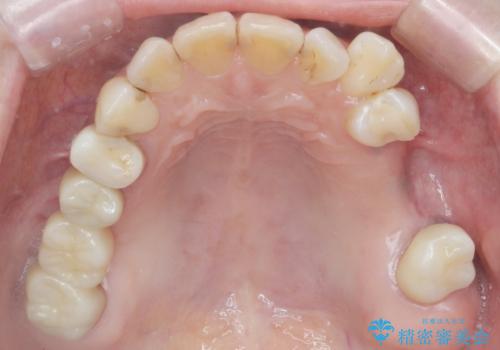

- 50代女性

- 以前から治療されている患者様です。

左上の小臼歯、大臼歯が欠損しているため。インプラントのご案内をさせてもらったところ外科的な処置は行いたくないとの事でしたので

部分入れ歯のご案内をしました。なるべく銀は見えたくないとの希望により保険の入れ歯ではなく自費の入れ歯(ノンクラスプデンチャー)を作製しました。